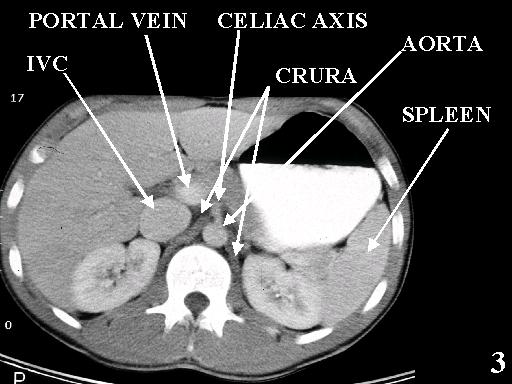

MS 190 CT 14